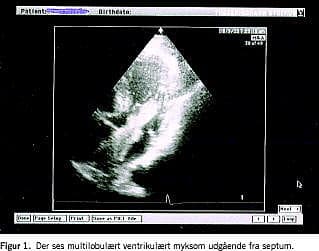

Grundet lang venteliste til transtorakal ekkokardiografi (TTE) og afbud fra patienten blev TTE'en først foretaget fem måneder efter udskrivelsen. Undersøgelsen viste et stort multilobulært myksom på 10 × 2 cm (Figur 1). Myksomet var udgående fra septum og strakte sig ned midt i venstre ventrikel. Fjorten dage senere blev det fjernet uden komplikationer.